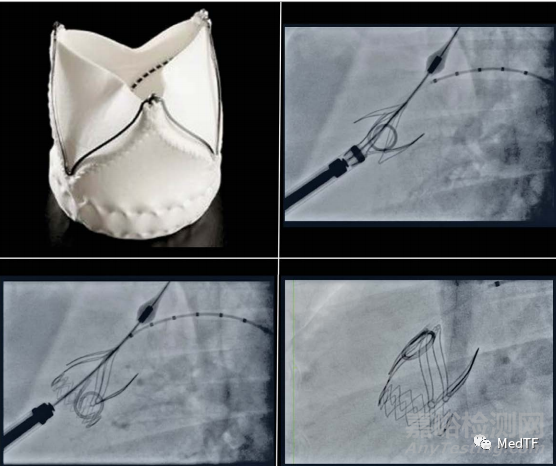

Xeltis PV

Xeltis PV是一種可吸收的植入物(瓣膜),其允許患者自身組織在植入物上定植,隨著時(shí)間形成進(jìn)化成功能齊全的天然心臟瓣膜,而可吸收的植入物(瓣膜)隨著時(shí)間逐步被降解吸收。

Xeltis PV由靜電紡絲技術(shù)制備,因此其擁有密密麻麻的多孔微結(jié)構(gòu),正是由于這些多孔微結(jié)構(gòu)存在,使得患者自身的組織能否快速填充到這些多孔微結(jié)構(gòu)中,并最終形成一個(gè)新的天然心臟瓣膜。

Xeltis PV的技術(shù)被稱為:內(nèi)源性組織修復(fù)(ETR),ETR是一種新的治療方法,能使患者自身的身體自然地恢復(fù)新的血管或心臟瓣膜。